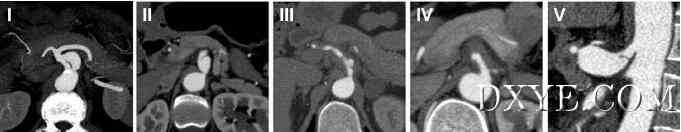

形态学发现和治疗的腹腔动脉(SIDCA)自发隔离夹层。在本回顾性研究中纳入2009年1月至2014年12月期间23例SIDCA患者。回顾了这些患者的人口统计学数据,临床特征,形态学结果,治疗方式和随访结果。我们提出了类似于肠系膜上动脉自发隔离解剖的SIDCA的形态学分类。 腹腔动脉自发性分离解剖形态学分类(SIDCA)。 I型,假腔同时进入和再入; II型,“死路”型假腔无再次进入; III型,具有溃疡样突起(ULP)的血栓性假腔; IV型,完全血栓形假腔,无ULP; 和V型,与解剖相关的动脉瘤发展。 保守治疗的IIIa型患者。 A,初始计算机断层扫描(CT); B,CT 6个月后; 和C,CT后12个月。 一个IIIb期患者血管内治疗。 A-C,解剖涉及腹腔干,脾动脉和肝动脉。 真腔几乎完全闭塞。 D和E,假腔消失,支架和分支在裸支架植入腹腔干和肝动脉。 结果在最初,11例患者接受血管内治疗,12例接受医疗治疗。四个医疗治疗患者的解剖出现加重,需要血管内抢救。所有患者均成功恢复。没有的患者出现腹痛,需要再次手术,或死亡。在医学治疗组中,假腔在4名患者中完全血栓形成并被吸收,部分血栓形成在2处。所有支架均获得专利,假腔完全血栓形成并在血管内组中被吸收。 该研究得出,SIDCA可以在稳定的患者中进行医学治疗,但需要密集随访。血管内治疗可应用于具有复发性症状,内脏灌注不足或动脉瘤的高危患者。如果血管内修复不合适或失败,应考虑开放手术。血管内管理的短期结果令人鼓舞,但需要进行长期随访的进一步评估。 |